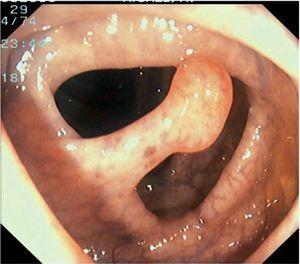

Fig. 4. Examples of protruding lesions with conventional examination and after the application of indigo carmine 0.2-0.5%. a, b) Sessile polyp. c, d) Subpedunculated polyp. e, f) Pedunculated polyp. g, h) Submucosal lesion (indigo carmine shows distinct innominate grooves, ruling out an epithelial lesion). i) Subpedunculated polyp. j) After indigo carmine application, a flat elevated lesion similar in size to the protruding segment is clarified.